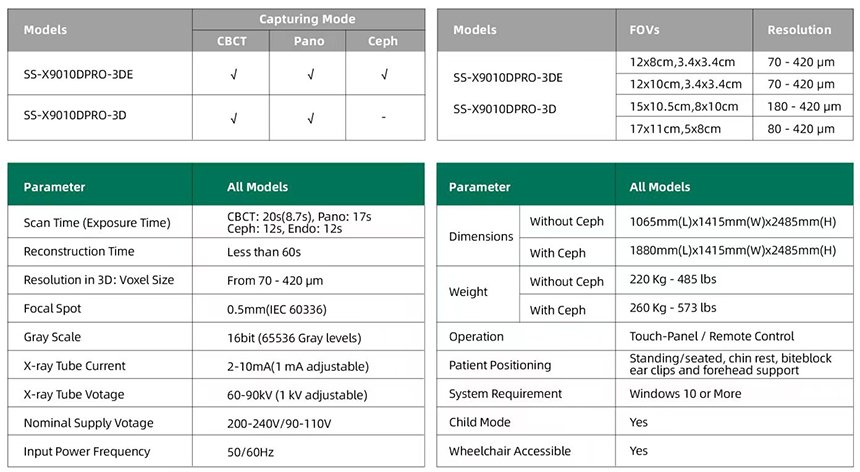

- Amplio campo de visión, satisfaciendo las necesidades clínicas generales.